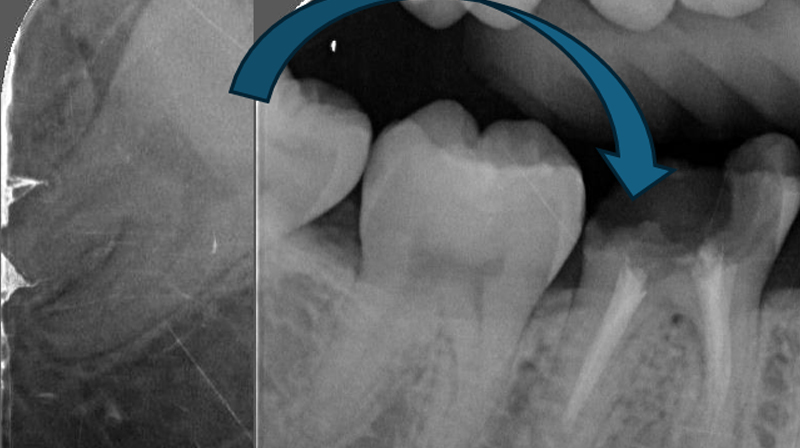

右下第一大臼齒斷裂

治療計畫

右下第一大臼齒拔除, 將右下智齒移植到缺牙區域

術前